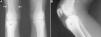

Un paciente varón de 15 años consultó por gonalgia derecha de ritmo mecánico, de 8 meses de evolución, de inicio intermitente y luego continua, que limitaba la deambulación, con tumefacción asociada en dicha localización. Se le indicó antiinflamatorios no esteroideos (AINE), inicialmente ibuprofeno y luego diclofenaco, de forma secuencial, sin mostrar mejoría. No refería antecedente traumático, fiebre o síntomas constitucionales, ni presentaba otra clínica articular periférica, axial o entesítica. Había sido diagnosticado de psoriasis guttata a los 10 años, con brotes ocasionales hasta los 13 años, tratados con glucocorticoides tópicos; sin embargo, no tenía antecedentes familiares de psoriasis, artritis psoriásica, espondilitis anquilosante o enfermedad inflamatoria intestinal. La exploración evidenció atrofia muscular en el muslo distal y tumefacción en la zona infrapatelar derecha, con aumento de calor local y limitación en los últimos grados de flexión, pero sin signos de derrame articular. La analítica, incluyendo bioquímica, hemograma y reactantes de fase aguda (velocidad de sedimentación globular 6mm/h, proteína C reactiva 2,31mg/dl) fue normal. El tipaje HLA demostró que era portador de los haplotipos Cw6, DR4 y DQ8, pero no B27, y los resultados de factor reumatoide y anticuerpos antinucleares fueron negativos. En la radiografía simple de las rodillas se observaba una zona esclerosa en el tercio superior de la tibia derecha (figs. 1A y B), que en la tomografía computarizada (TC) correspondía a una lesión osteolítica de 5mm de diámetro en la tuberosidad tibial anterior, con matriz osificada a modo de «nidus», compatible con OO (figs. 2B y C), con importante esclerosis del hueso medular y reacción perióstica sólida en la cortical adyacente. En la resonancia magnética había intensa captación perilesional de contraste, así como en el edema óseo circundante y la grasa de Hoffa (figs. 2C y D). La gammagrafía ósea objetivó hiperemia y aumento focal de reacción osteogénica en la epífisis proximal de la tibia derecha, sin alteraciones significativas en otra parte. El paciente fue sometido a ablación por radiofrecuencia guiada por TC, con desaparición del dolor pocos días después del procedimiento y recuperación completa de la movilidad al mes, aunque con leve atrofia muscular persistente.